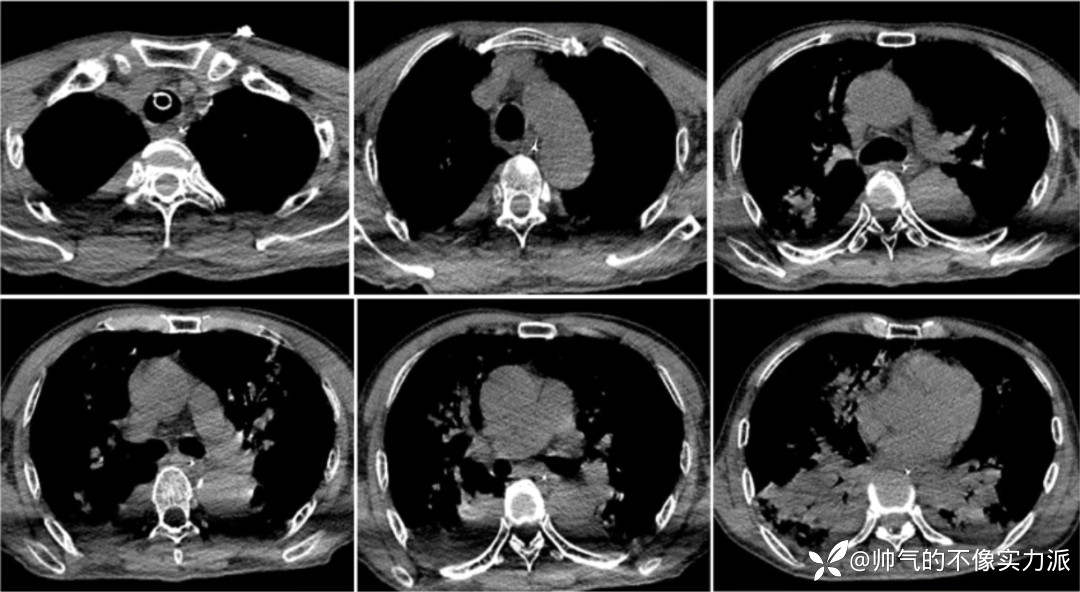

- 考虑患者有无肺栓塞可能?故进一步完善CT肺动脉造影(CTPA)检查,结果提示右肺下叶动脉内低密度充盈缺损,考虑栓子形成可能。双肺炎症并部分肺实变,建议治疗后复查。

- 2020年12月12日,复查胸部CT:双上肺磨玻璃影明显增多,下肺重力依赖区依然存在实变影,少量胸腔积液(图3)。

图3 患者胸部CT(2020-12-12)

- 复查胸部CT(2020-12-16):双上肺病变仍然较重,双下肺重力依赖区实变影明显吸收,双侧少量胸腔积液(图5)。

图5 患者胸部CT(2020-12-16)